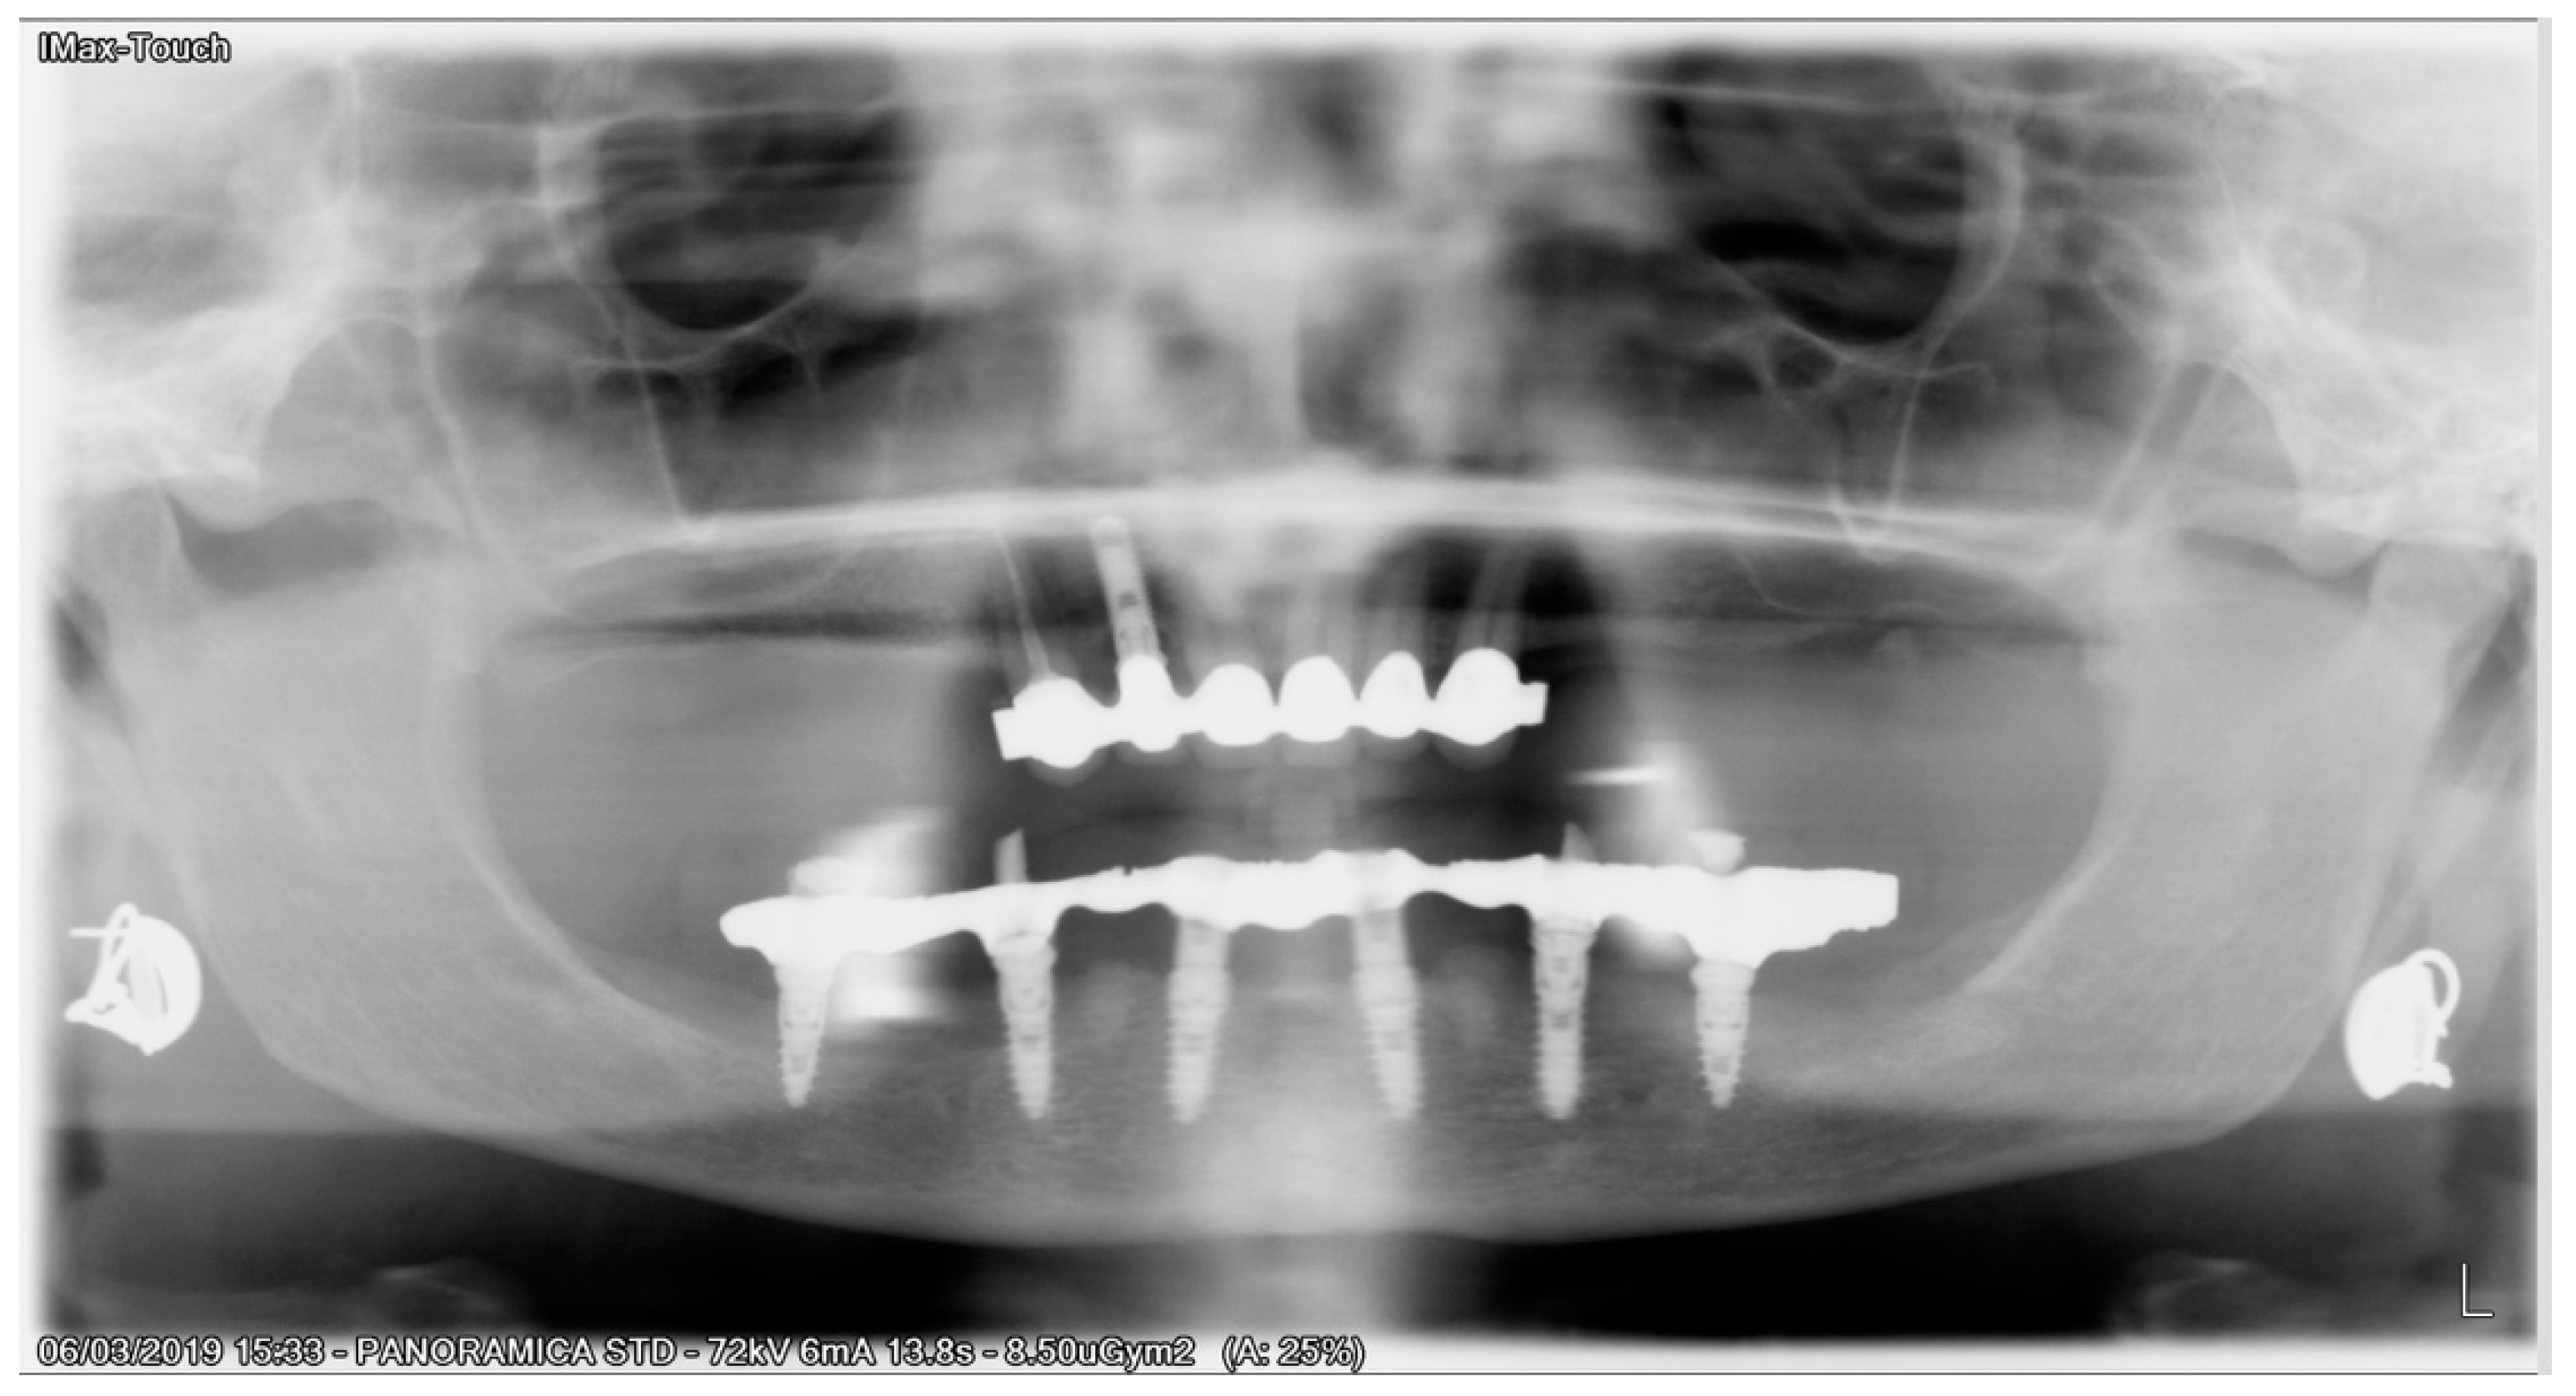

Six months after surgery, all temporary restorations were replaced with final prosthetic restorations (Figure 7).

Figure 7. 2 years postoperative panoramic X-ray.